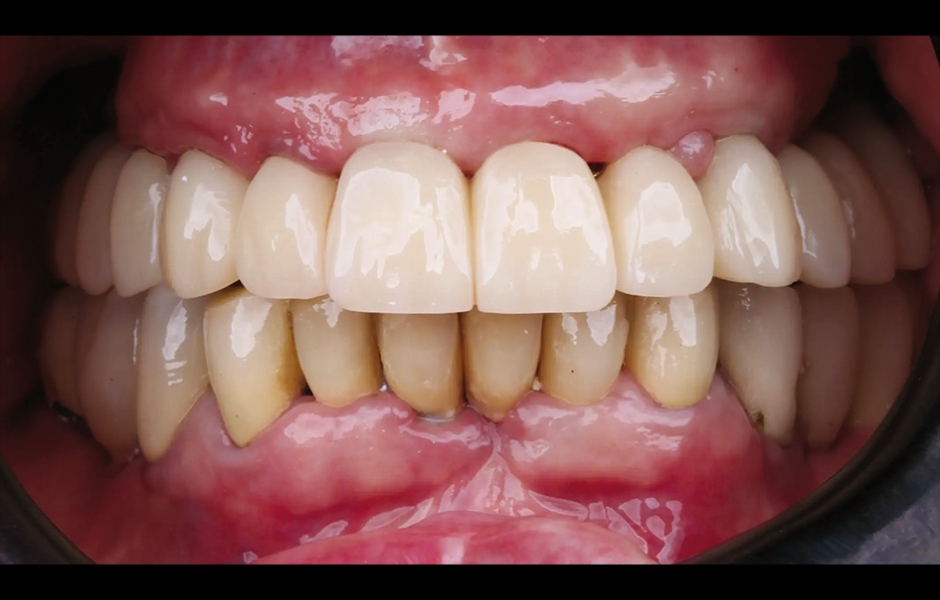

Při finální návštěvě byla nasazena definitivní hybridní šroubem fixovaná protetika. Definitivní práce sestávala z CAD/CAM titanového skeletu přišroubovaného na všechny implantáty a tří monolitických zirkoniových segmentů vlepených nahoře (obr. 18a–c). Byla zkontrolována okluze a pacient byl zařazen do čtyřměsíčního recall programu. Při poslední kontrole (rok po implantaci) byly všechny implantáty úspěšné a pacient byl plně spokojen s novou protetikou (obr. 19–22).

Obr. 19: Definitivní protetická práce při jednoroční kontrole, frontální pohled.

Obr. 20: Definitivní protetická práce při jednoroční kontrole, okluzální pohled.